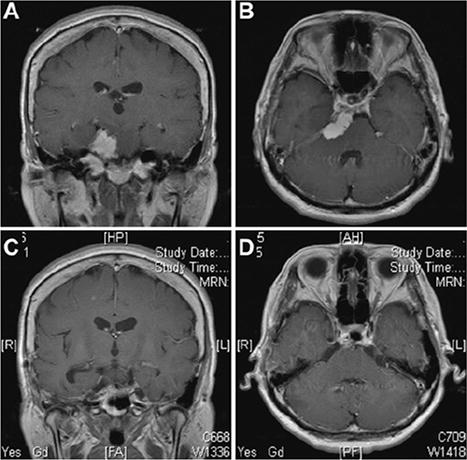

53歲女性,表現(xiàn)為悸動性頭痛,并觀察到左眼視力急劇下降。MRI顯示一個均勻增強的腫塊,集中在巖斜上交界處,廣泛植入并附著在上斜坡和天幕上(圖5A和B)。進行了Kawase入路。在滑車神經(jīng)入幕附近行小腦幕切口后,可見三叉神經(jīng)向雙側(cè)下移位,部分被腫瘤包裹,與上斜坡相連,部分鈣化。外展神經(jīng)在切除腫瘤后被觀察到向下移位。MRI(圖5C和圖D)顯示腫瘤完全切除,無任何腦損傷?;颊咝g(shù)后出現(xiàn)部分側(cè)視麻痹,1個月后完全消失,恢復正常。腫瘤起源于硬膜內(nèi)間隙,位于圖3中的B2和C1區(qū)。在這種情況下,Kawase入路是一種合適的方法。

案例1。Kawase入路手術(shù)切除腫瘤。術(shù)前MRI冠狀位(A)和軸位(B)增強圖像提示巖斜區(qū)一均勻強化的腫瘤,起源于巖尖,附著在小腦幕上。腫瘤推擠腦干,侵犯海綿竇。術(shù)后MRI(C和D)顯示腫瘤全切。